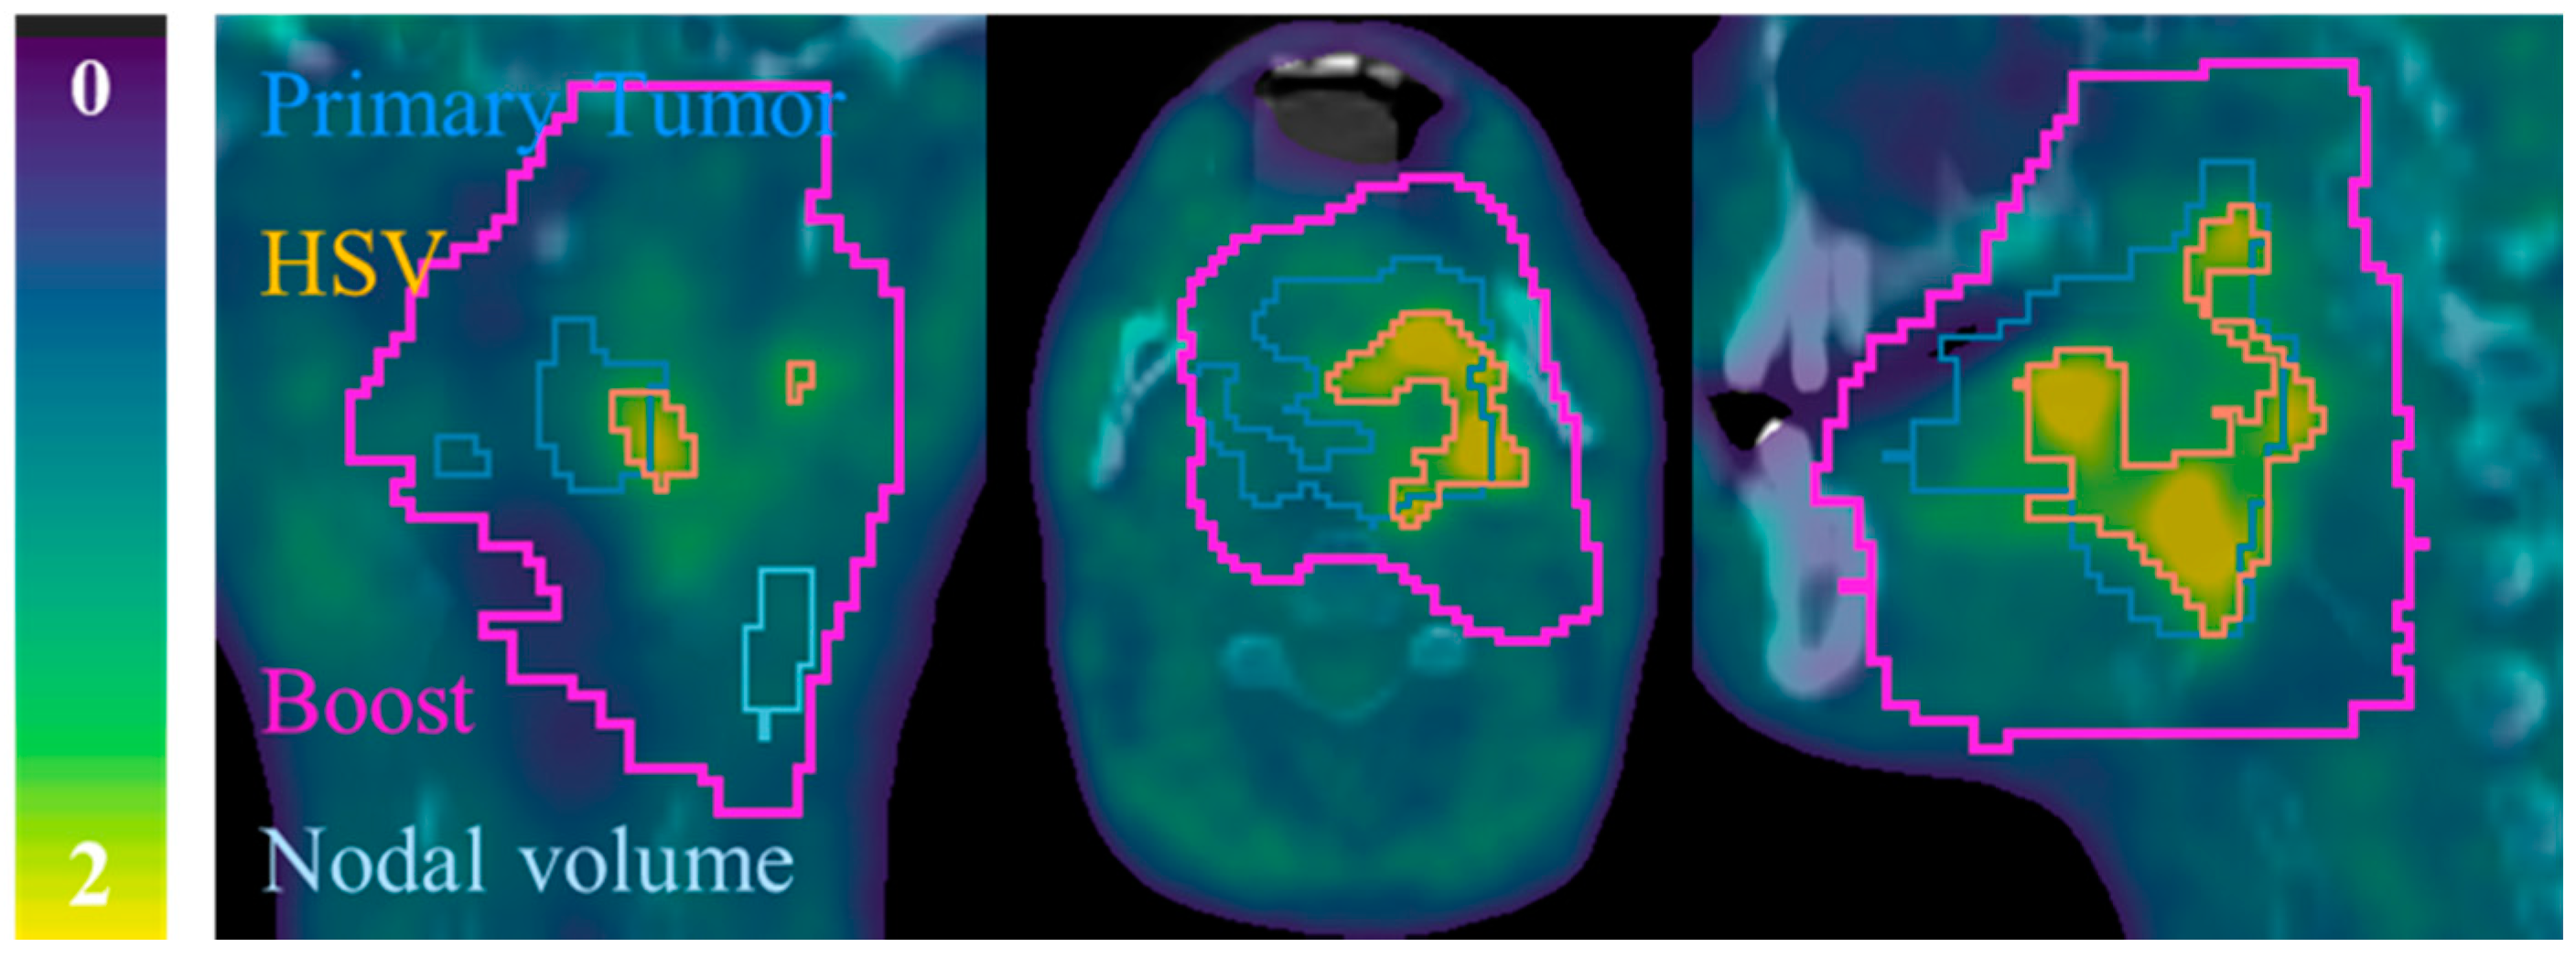

2.3. Segmentation

Appendix A. Automatic FMISO Segmentation Using the Parotid Contour from Radiotherapy Planning

- Firstly, CT from radiotherapy planning is co-registered with FMISO-image by the corresponding CT and contralateral parotid contour (Vparotid) is transferred to all FMISOs.

- Then, for each voxel of Vparotid the intensities derived from the tree FMISOs (W0, W2 and W5) were multiplied and voxels that resulted in zero were removed from the contour. This step took into account the possibility of having part of the Vparotid out of the FMISO image.

- Finally, the background (Bgparotid) was defined selecting the voxels with highest uptake until filling a volume of 6 mL. By focusing on higher uptake voxels, we could minimized the partial volume effect (PVE) given in voxels in the peripheral zone of the body and the co-registration error. Additionally, a volume of 6 mL permitted to minimize the PVE in the computation of SUVmean.